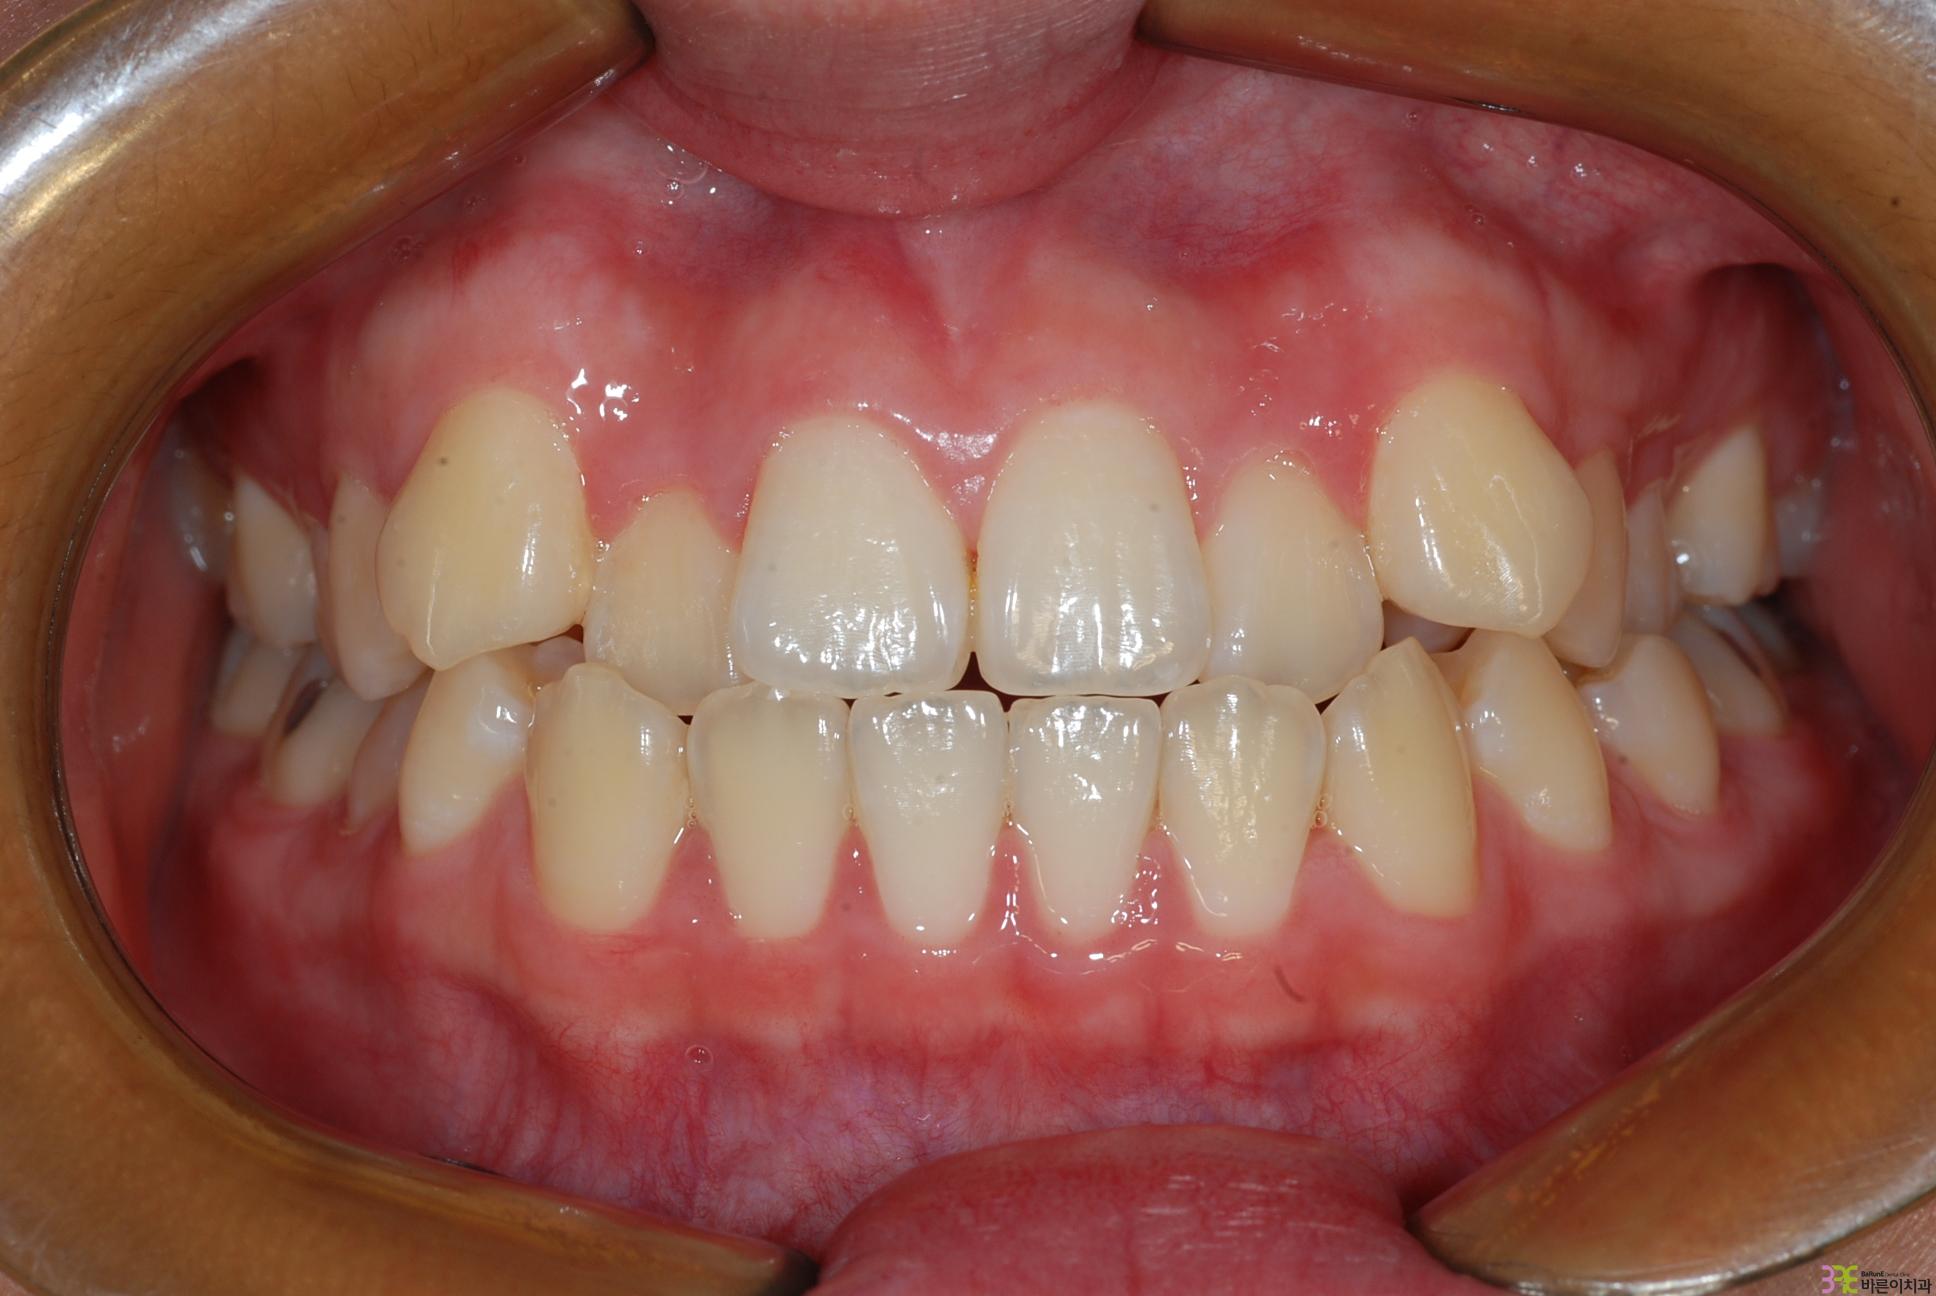

치료명

덧니교정

치료기간

1년

Before

After